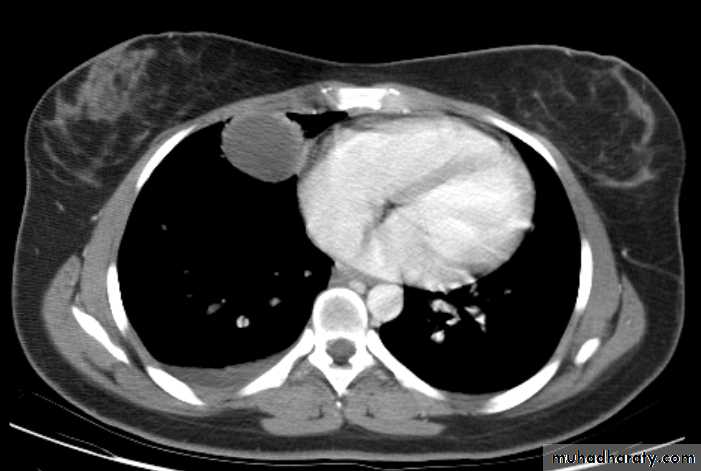

Pericardial cyst

Vascular and chest surgery practical